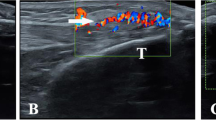

Although the best imaging method to investigate the presence of MSU crystal deposits in the early stages has not yet been established [5], ultrasound (US) has been demonstrated to be a valid imaging modality to detect musculoskeletal involvement in patients with gout [6–9]. The main US findings related to MSU crystal deposition include hyperechoic enhancement of the superficial margin of the hyaline cartilage (double contour sign), hyperechoic spots within tendons and soft tissues, tophi and bone erosions [7, 10, 11]. Additionally, an increase of blood flow surrounding the MSU deposits detected by power Doppler (PD) has been described as an indicator of inflammatory activity [5, 7].

On femoral hyaline cartilage, the double contour sign (Figure 1A) was present in 17 of 100 knees from hyperuricemic patients in contrast to none in the control group (P < 0.0001), giving an odds ratio (OR) of 43.8 (95% confidence interval (95% CI), 2.9 to 739). The prevalence of the double contour sign in the first MTPJs (Figure 1B) was also higher in hyperuricemic patients (25% vs. 0%; P < 0.0001), with an OR of 34.3 (95% CI, 4.5 to 259). However, no correlation between SU concentration and the presence of the double contour sign was found (rs -0.06; 95% CI, -0.3 to 0.2).

Tendon examinations showed patellar enthesopathy (12% vs. 2.9%; P = 0.01) and intratendinous tophi (6% vs. 0; P = 0.01), as well as Achilles enthesopathy (15% vs. 1.9%; P = 0.0007), to be more frequent in hyperuricemic patients than in normouricemic individuals (Table 3). Tenosynovitis was found only in three hyperuricemic patients (two in the peroneus longus tendon and one in the posterior tibialis tendon). No PD signal was found in any anatomical area examined.

Chronically elevated SU has not usually been considered to play a pathogenic role in tissue damage. However, large prospective population studies are challenging this notion, since they have found that SU levels are reliable and consistent predictors of progression for endothelial dysfunction [16], coronary artery disease [17, 18] and renal failure [2]. In this line of thought, our results support the existence of both intra- and extra-articular tissue damage caused by the persistent elevation of SU [5]. The presence of MSU crystals in the synovial fluid from asymptomatic individuals with hyperuricemia has been demonstrated on the basis of polarized light microscopy since the early 1980s [4]. In accord with this evidence, the double contour sign has been described solely in gout and seems to represent the preference of SU to crystallize on the surface of cartilage [7, 11, 19]. Even when the underlying mechanisms for this preference need further clarification, it has been shown that the normal components of cartilage chondroitin sulfate and phosphatidylcholine facilitate the nucleation and subsequent crystallization of MSU [20]. As confirmation of the presence of MSU in the hyaline cartilage, Thiele and Schlesinger [21] recently demonstrated the disappearance of the double contour sign in patients with gout successfully treated with urate-lowering agents who had maintained SU levels below 6 mg/dL for at least 7 months. Also, tophi formation detected in our study further confirmed the presence of MSU crystal tissue deposition in both intra- and extra-articular structures from asymptomatic hyperuricemic individuals as previously suggested [5]. This may strengthen the need for treatment necessity in asymptomatic individuals with hyperuricemia and indisputable US features of MSU crystal tissue deposition such as the double contour sign or the presence of tophi [3].